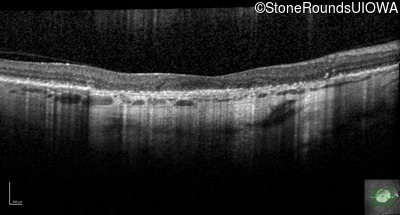

Optical Coherence Tomography - Right - 20/63

Exemplar / OCT Stack